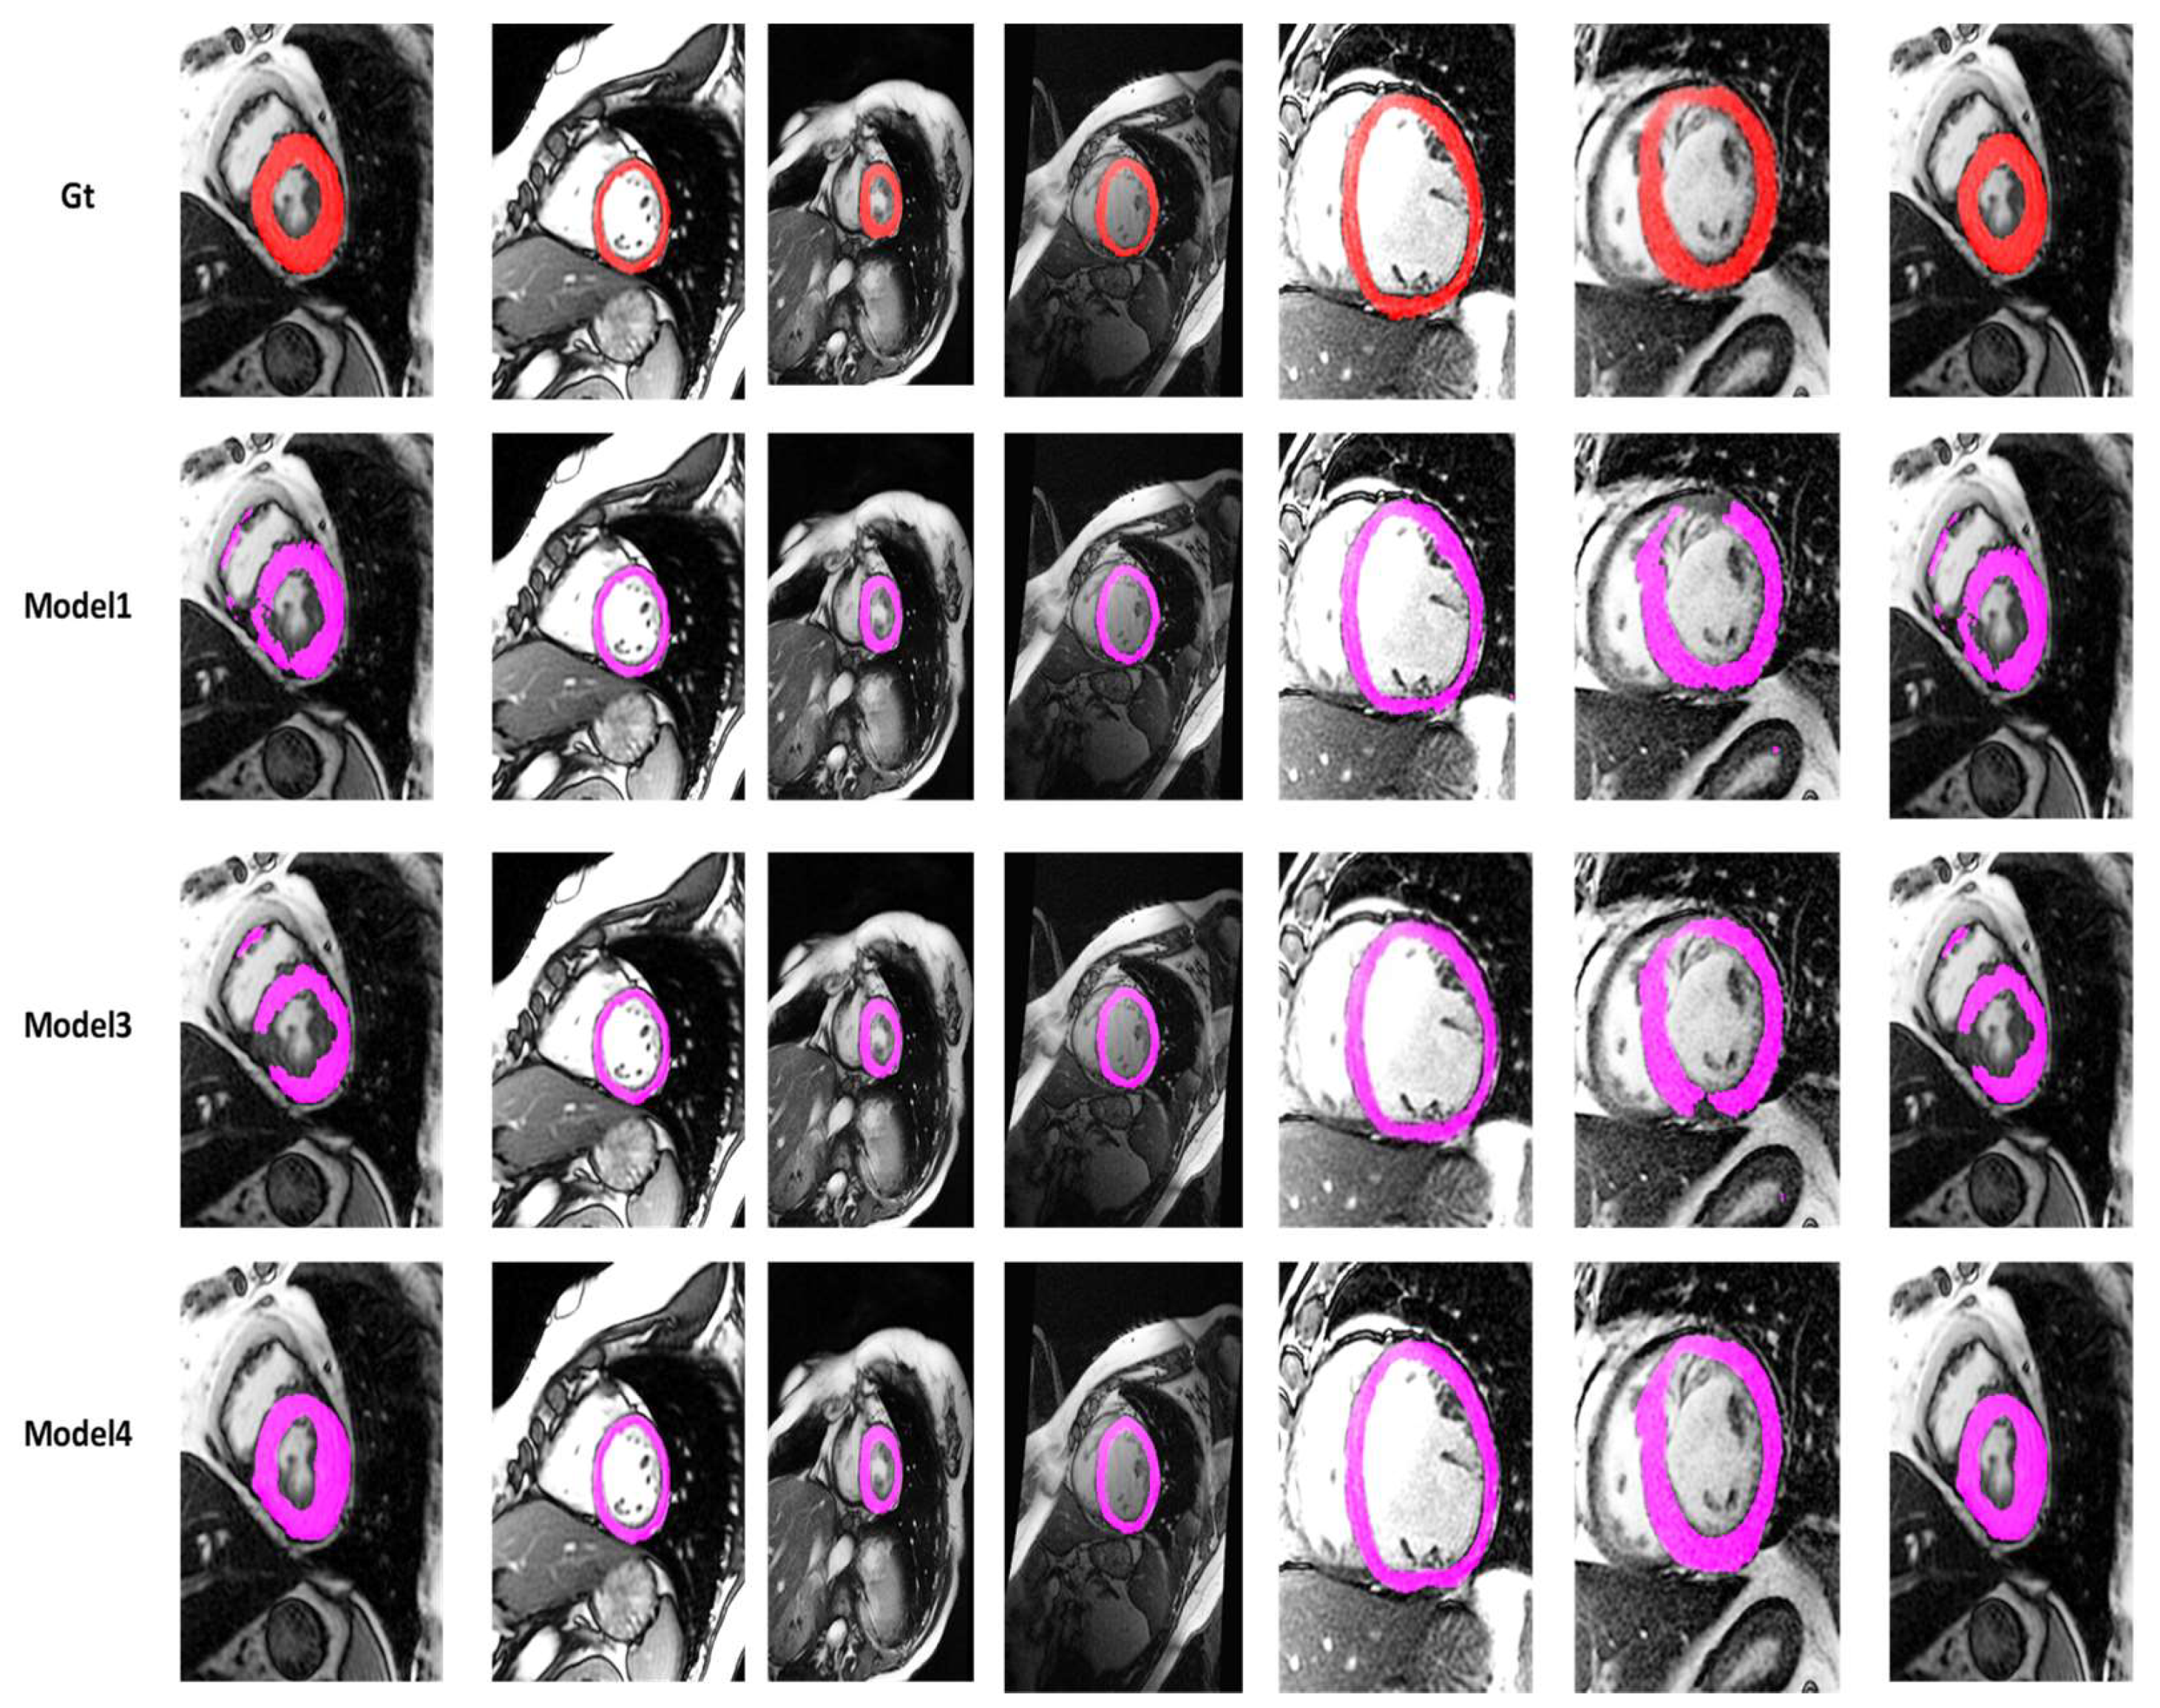

4.2. Visualization Segmentation Results

| ProposedM4 | 85.43 | 75.93 | 6.1702 | 10.0142 | 99.14 | 85.51 | 0.2406 | 1.7823 | 0.0141 |

| FractalNetM3 | 83.63 | 73.88 | 13.1938 | 20.2024 | 99.04 | 83.18 | 0.2611 | 2.9740 | 0.0169 |

| ProposedM3 | 84.96 | 74.78 | 11.3915 | 24.4692 | 98.97 | 87.48 | 0.2521 | 2.3937 | 0.0795 |

| FactalNetM1 | 81.91 | 71.38 | 9.2453 | 30.4901 | 98.60 | 85.92 | 0.2861 | 2.80443 | 0.1231 |

| ProposedM1 | 82.51 | 71.80 | 11.4752 | 26.905 | 98.76 | 87.22 | 0.2819 | 2.7359 | 0.1746 |